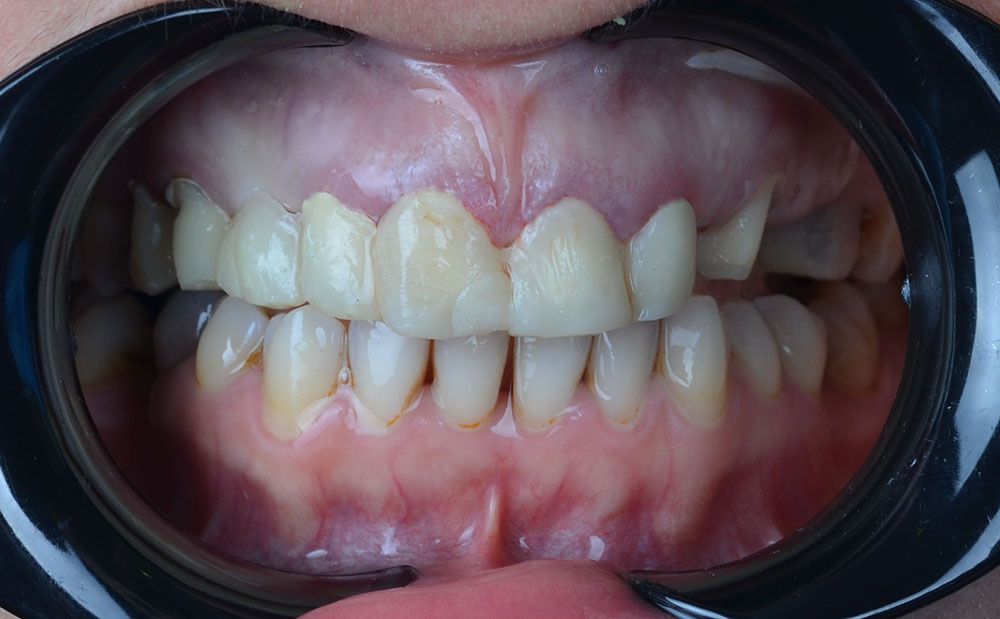

She contact to us with the complaint of her maxillary teeth. After careful examinations we decided that she has gingivitis and her previous crowns were not natural and fitting well. But also she was not sure about us. So we took her photos and initial impressions and send them to our lab for creating a smile model.

Our lab send us a model that shows us the final form of her teeth after 3 days. We showed it to our patient and she liked the final result. So after she confirm the treatment we decided to start with periodontal treatment and gingivectomy. After 7 days of healing, we started preperations and took our impressions to send it back to the lab. The lab produced the same teeth we showed our patient before by replicating the previous teeth design. So our patient had the teeth we showed her before by only waiting 3 more days and also for some extra cost. But the result was for good.